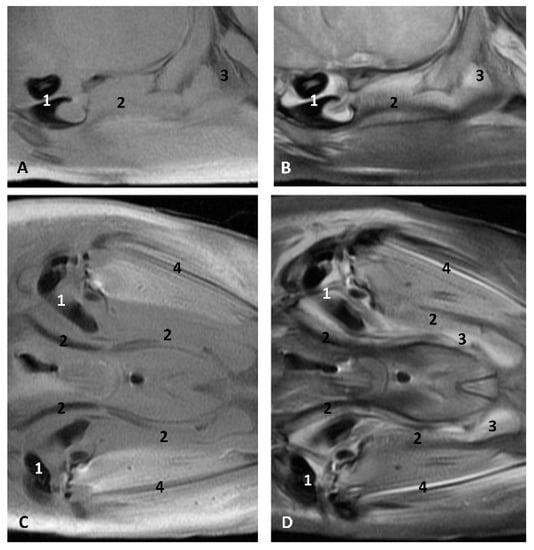

Figure 26. Images of the pharyngeal cavity. MR sagittal and coronal images are oriented so that the rostral is to the right. (A) T1 SE sagittal, (B) T2 FrFSE sagittal, (C) T1 SE coronal and (D) T2 FrFSE coronal planes. 4 months, dde3. 1, Inner and middle ear; 2, Pharyngeal diverticulum of the auditory tube.

In MRI, we can appreciate, in early fetal stages, a bilateral structure within the laryngopharyngeal cavity, each named as a pharyngeal diverticulum of the auditory tube (PDAT). These are connected through the musculotubaric channel with the middle ear (temporal bone: petrous and tympanic part). In a young Delphinus delphis fetus (dde3), it appears in sagittal sections as a hyper/hypointense area seen caudal and rostrally, respectively (Figure 26A,B), and also in coronal sections (Figure 26C,D).

In older Delphinus delphis fetuses (dde5, dde8, dde11) this double space at both sides of the laryngopharynx is more evident and shows the same intensity, but now we can distinguish the vascular area (hyperintense) and the air-filled area (hypointense) (Figure 27, Figure 28, Figure 29, Figure 30 and Figure 31).

In more advanced fetal development, it is possible to observe air (hypointense) and vascular (moderate hyperintense) areas, and even the auditory tube (slightly hypointense) (Figure 30).

PDAT were clearly seen in sagittal and coronal sections in a Grampus griseus fetus (grgr1). The T2 sequences are clearer than T1 because they differentiate two areas: slightly hypointense (vascular) and hyperintense (air) (Figure 31).